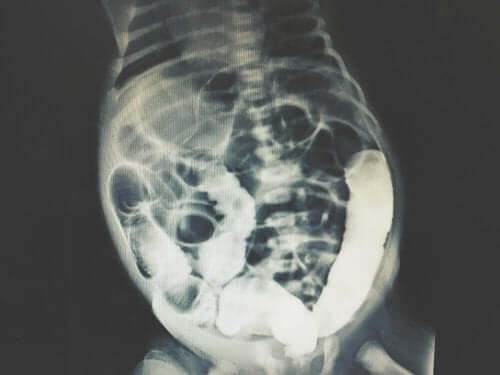

Peritoneal skylling innebærer en svært pålitelig medisinsk undersøkelse. I tillegg produserer det en minimal mengde falske positiver eller andre feil. Det brukes vanligvis sammen med annen diagnostisk medisinsk bildediagnostikk, og kan foregå som en CT (datastyrt tomografi) skanning eller MR (Magnetic Resonance Imaging).

Avhengig av resultatene, kan ekspertgruppen bestemme årsaken til mageproblemene. De kan også utføre tester for å få interne bilder av mageregionen. På denne måten kan de lette diagnosen.